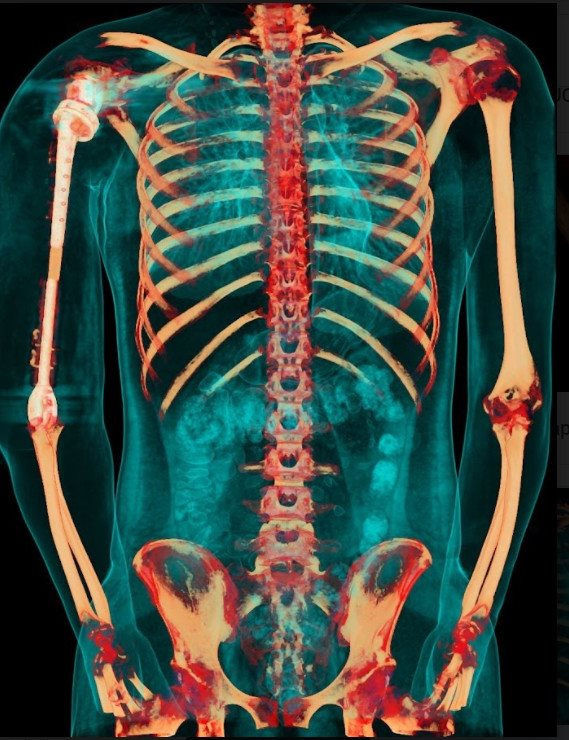

Ảnh chụp X-quang so sánh xương cánh tay 2 bên sau khi phẫu thuật

Ca phẫu thuật phục hồi cánh tay cho bệnh nhân V.T.Đ. là ca bệnh đầu tiên trên thế giới sử dụng kết hợp vật liệu giữa hợp kim titan và vật liệu y sinh PEEK do các bác sỹ của Trung tâm CTCH&YHTT Vinmec thực hiện

Việc sử dụng kết hợp 2 loại vật liệu trên cùng một xương nhân tạo để tận dụng được ưu điểm tối đa: tính vận động chính xác, linh hoạt của hợp kim titanium tại vùng khớp, và đặc tính nhẹ, bền, tương thích với cơ thể của vật liệu PEEK. Nhờ vậy, trọng lượng cánh tay nhân tạo có thể giảm xuống còn 1 nửa và chi phí giảm tới hơn 1/3 so với việc chỉ dùng vật liệu kim loại như trước đây.